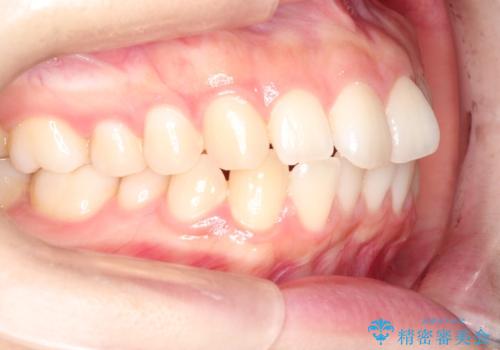

前歯のがたつきをインビザラインで目立たない矯正

- 上下の前歯のがたつきを主訴に来院されました。

マウスピースでの矯正を希望されたので、インビザラインで矯正治療を行うこととしました。

インビザラインではシュミレーションによりどのように歯が動くかを確認して矯正することができるので、患者様も安心して矯正をすることができました。